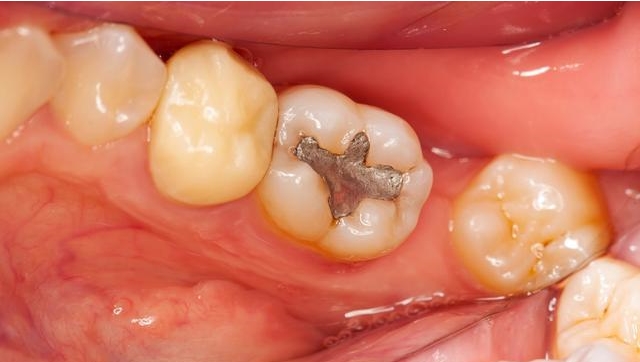

牙齿充填时的并发症及处理 充填术是治疗龋病的有效方法。在治疗过程中,根据患牙龋损的具体情况,作出正确的诊断和相应的治疗方案,按照正规程序进行处理,一般情况下,是不会出现问题的。如诊断不正... 牙齿治疗 捷思若 1393 2024-03-06

龋齿治疗都有哪些方法 龋齿是一种慢性进行性疾病,一旦发生龋齿,不能自行修复,需进行治疗。龋病治疗的目的在于终止病损的发展,保护牙髓,并利用材料恢复牙齿的形态及功能。龋齿治疗的方法包括... 牙齿治疗 仪捷 761 2024-01-08

龋病的治疗方法是什么 牙齿硬组织破坏后,缺乏再生能力,一般需人工修复。治疗的目的在于停止病变的发展,并利用充填材料充填窝洞,恢复牙齿的外形和功能,保护牙髓的正常活力,维护牙列的完整。... 口腔资讯 充向雪 582 2023-12-15